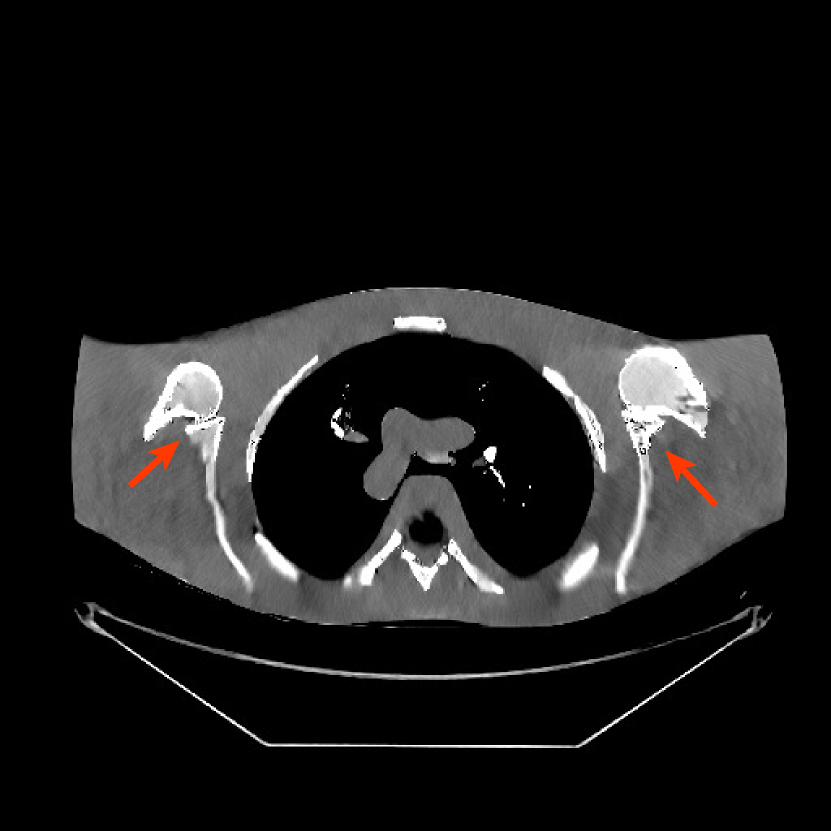

Figure 10: Reconstructions for ultra low-dose 2D scan simulated from raw measurements. The leftmost image is the PWLS-EP reconstructed image for the 200 mA200 mA200\text{ mA} scan. The second image is the PWLS-EP reconstruction for the simulated ultra low-dose scan, and it is the initial image for WavResNet [46], PWLS-ULTRA [38], and SPULTRA. The display windows are [800, 1400] HU.

TABLE III: Mean (HU) and standard deviation (STD) (HU) of the ROIs for ultra low-dose shoulder phantom simulations.

(a) Mean (HU)

Methods ROI 1 ROI 2 ROI 3

Reference 1052.1 1060.1 1053.4

PWLS-EP 1032.7 977.5 1026.3

WavResNet[46] 1037.6 981.1 1031.2

PWLS-ULTRA[38] 1031.1 1043.0 1024.2

SPULTRA 1054.7 1044.0 1049.6

(b) STD (HU)

Reference 8.12 8.81 6.98

PWLS-EP 19.45 19.45 30.46

WavResNet[46] 18.91 18.91 30.16

PWLS-ULTRA[38] 14.82 10.92 19.29

SPULTRA 16.34 11.42 11.60

V-C2 Results

Fig. 10 shows the reconstructions for the 200 mA200 mA200\text{ mA} scan (reference image) along with the reconstructions for the simulated ultra low-dose scan obtained with PWLS-EP, WavResNet, PWLS-ULTRA, and SPULTRA. Visually, WavResNet fails to reconstruct the image but improves over the initial PWLS-EP reconstruction, while PWLS-ULTRA and SPULTRA provide better image quality. This indicates that the ULTRA-based methods may have a better generalization property than WavResNet, since they learn more fundamental features of CT images (also see [38]). We selected three smooth ROIs, where the pixel values are approximately constant. Tab. V(b) shows the mean and the standard deviation of pixel values for these ROIs for various methods and the standard-dose reference. Since the iterative RNN version of WavResNet only has small improvements over PWLS-EP, the pixel values do not change much compared with PWLS-EP. PWLS-ULTRA however reduces the bias in the central region of the image (ROI 2), but fails to correct the bias in the regions near the bones (ROI 1 and ROI 3). SPULTRA reduces the bias in the central region of the image, and also significantly corrects the bias near the bone regions. The standard deviations of the ROIs reconstructed by SPULTRA are comparable to those reconstructed by PWLS-ULTRA, and are close to those of the reference ROIs. Additionally, SPULTRA reconstructs the bone (indicated by the magenta arrow in the last two subfigures of Fig. 10) better than PWLS-ULTRA.